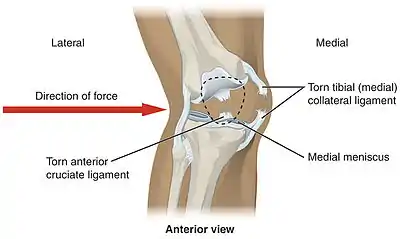

In sports that place great pressure on the knees, especially with twisting forces, it is common to tear one or more ligaments or cartilages. Some of the most common knee injuries are those to the medial side: medial knee injuries.[29]

Anterior cruciate ligament injury

The anterior cruciate ligament is the most commonly injured ligament of the knee. The injury is common during sports. Twisting of the knee is a common cause of over-stretching or tearing the ACL. When the ACL is injured a popping sound may be heard, and the leg may suddenly give out. Besides swelling and pain, walking may be painful and the knee will feel unstable. Minor tears of the anterior cruciate ligament may heal over time, but a torn ACL requires surgery. After surgery, recovery is prolonged and low impact exercises are recommended to strengthen the joint.[30]